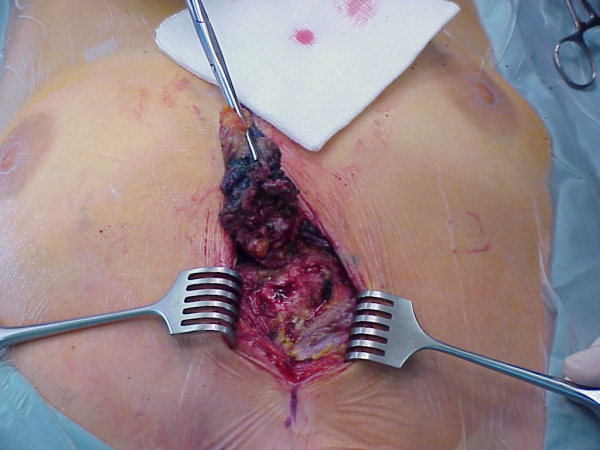

Bei einer tief greifenden Infektion, symptomatisch durch Brustschmerzen, Fieber, Sternuminstabilität oder eitriges Drainagesekret ist eine rasche operative Revision nötig (Abbildung 15 [Abb. 15]). Bei Nachweis von Knochennekrosen (Ostoemyelitis) ist ein „offenes“ Verfahren zu wählen, um die Infektion zu kontrollieren und eine Mediastinitis abzuwenden. Die Curretage (Abbildung 16 [Abb. 16]) der Nekrosen bzw. Knochensequester ist dabei essentiell, ebenso die Entfernung der Drahtcerclagen. Durch Methylenblauinstillation lassen sich Fistelgänge darstellen, die sorgfältig abgetragen werden müssen (Abbildung 17 [Abb. 17]). Durch regelmäßige Tamponadenbehandlung mit aseptischen Lösungen kann die Wunde durch sekundäre Granulation zur Ausheilung gebracht werden. Diese Methode ist aber sehr zeitaufwendig. Bei nicht beherrschbaren Nekrosen muss ggf. als Ultima ratio-Maßnahme die partielle oder sogar totale Sternektomie erwogen werden.

Abbildung 15: Sternuminfektion

Abbildung 16: Sternumcurretage

Abbildung 17: Nekrosektomie nach Fisteldarstellung mit Methylenblau